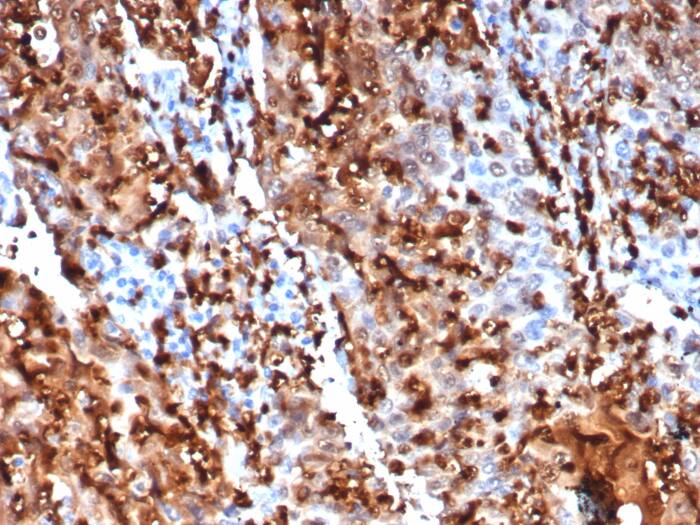

Formalin-fixed, paraffin-embedded human kidney stained with S100P Recombinant Mouse Monoclonal Antibody (S100P/7373). HIER: Tris/EDTA, pH9.0, 45min. 2: HRP-polymer, 30min. DAB, 5min.S100P Antibody (S100P/7373) - Azide and BSA Free